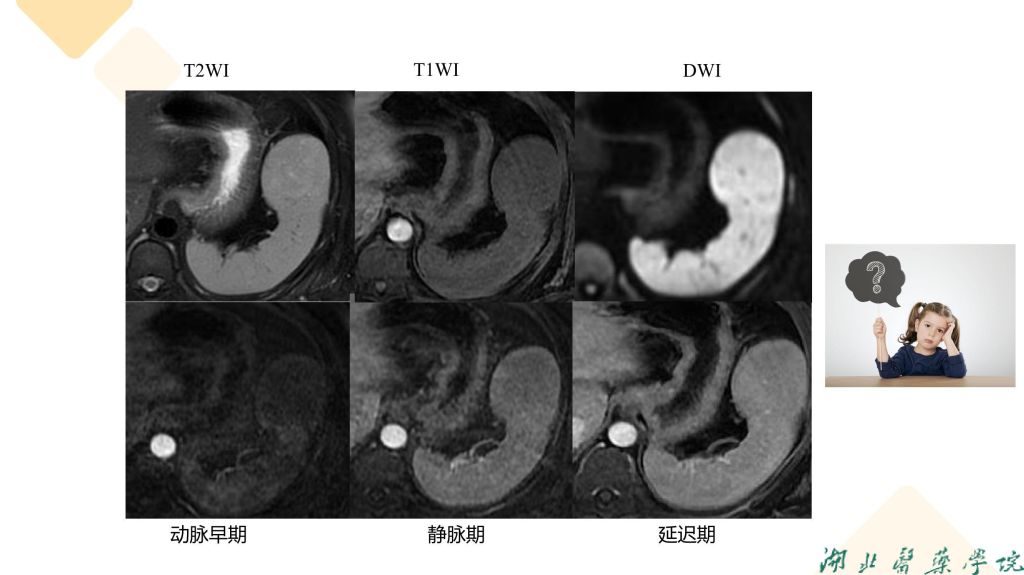

病例分享-脾脏实质性占位性病变

杨雪君 7790必发集团

病例分析-脾脏实性占位性病变-杨雪君.pdf